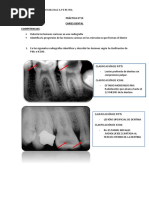

▪ Los materiales dentales, ▪ Los materiales de ▪ Los materiales

restauraciones e restauración radiolúcidos son:

instrumentos dentales se radiopacos son: oro, acrílico, silicatos,

fabrican de materiales amalgama de plata, hidróxido de calcio,

radiolúcidos y radiopacos. cemento de fosfato porcelana y algunos

La densidad de las de zinc y Eugenol, materiales de

restauraciones que se puntas de plata, restauración

observan en las radiografías gutapercha, compuestos.

también depende del alambres metálicos,

espesor del material que se bandas de cobre y

interponga al paso de la coronas de aluminio.

emisión de rayos X.

Hidróxido de calcio y

resina compuesta

contienen una adición de

material radiopaco que

proporciona al material de

obturación la suficiente

capacidad para absorber

rayos X, EN ESTA RADIOGRAFIA PODEMOS

VER COMO SE OBSERVA LA

AMALGAMA.